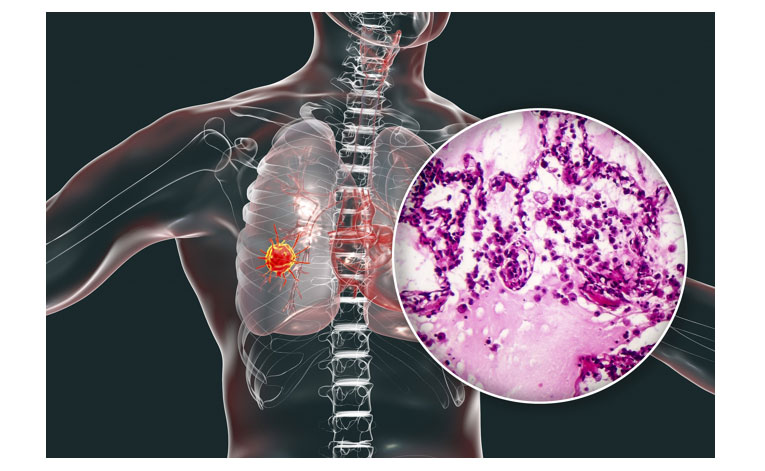

سرطان های ریه بر اساس بافت شناسی به چهار نوع سلول اصلی طبقه بندی می شوند: SCLC (که حدود 20 درصد سرطان های ریه را تشکیل می دهد و منشأ سلولی نورواندوکرین دارد)، آدنوکارسینوم ریه، سرطان ریه سلول سنگفرشی (SQC) و سرطان ریه سلول بزرگ. سه نوع آخر با هم به عنوان NSCLC گروه بندی می شوند.NSE در حال حاضر قابل اعتمادترین نشانگر تومور در SCLC است، حتی اگر یک بیومارکر ایده آل نیست. هنگام تشخیص (در 75 درصد بیماران هنگام تشخیص افزایش می یابد) و در پیش آگهی و پیگیری SCLC مفید است.

سطحNSE با اندازه تومور و تعداد مکانهای متاستاتیک مرتبط است و همبستگی خوبی بین کاهش اولیه غلظت پلاسما و پاسخ به درمان پیدا شد.